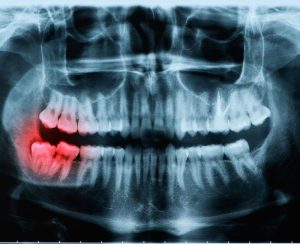

In some cases, wisdom teeth may only partially emerge, leaving a flap of gum tissue covering the tooth. This flap can trap food particles and bacteria, leading to gum infections, further exacerbating the pain and swelling. Impacted wisdom teeth, where the tooth does not have enough space to emerge correctly, can also be a source of discomfort. Impacted teeth may grow at an angle, pressing against other teeth, and potentially causing damage to the surrounding dental structures.

In some instances, individuals may develop cysts or tumours around impacted wisdom teeth, which can lead to further complications and heightened discomfort. If left untreated, these issues can cause damage to the jawbone and other teeth, making prompt intervention essential.